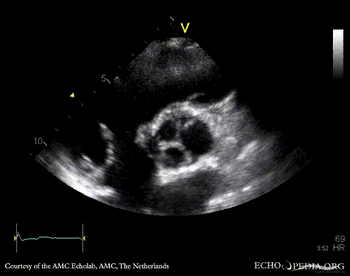

PSAX: bicuspid aortic valve with raphe PSAX: Color Doppler, mild aortic regurgitation